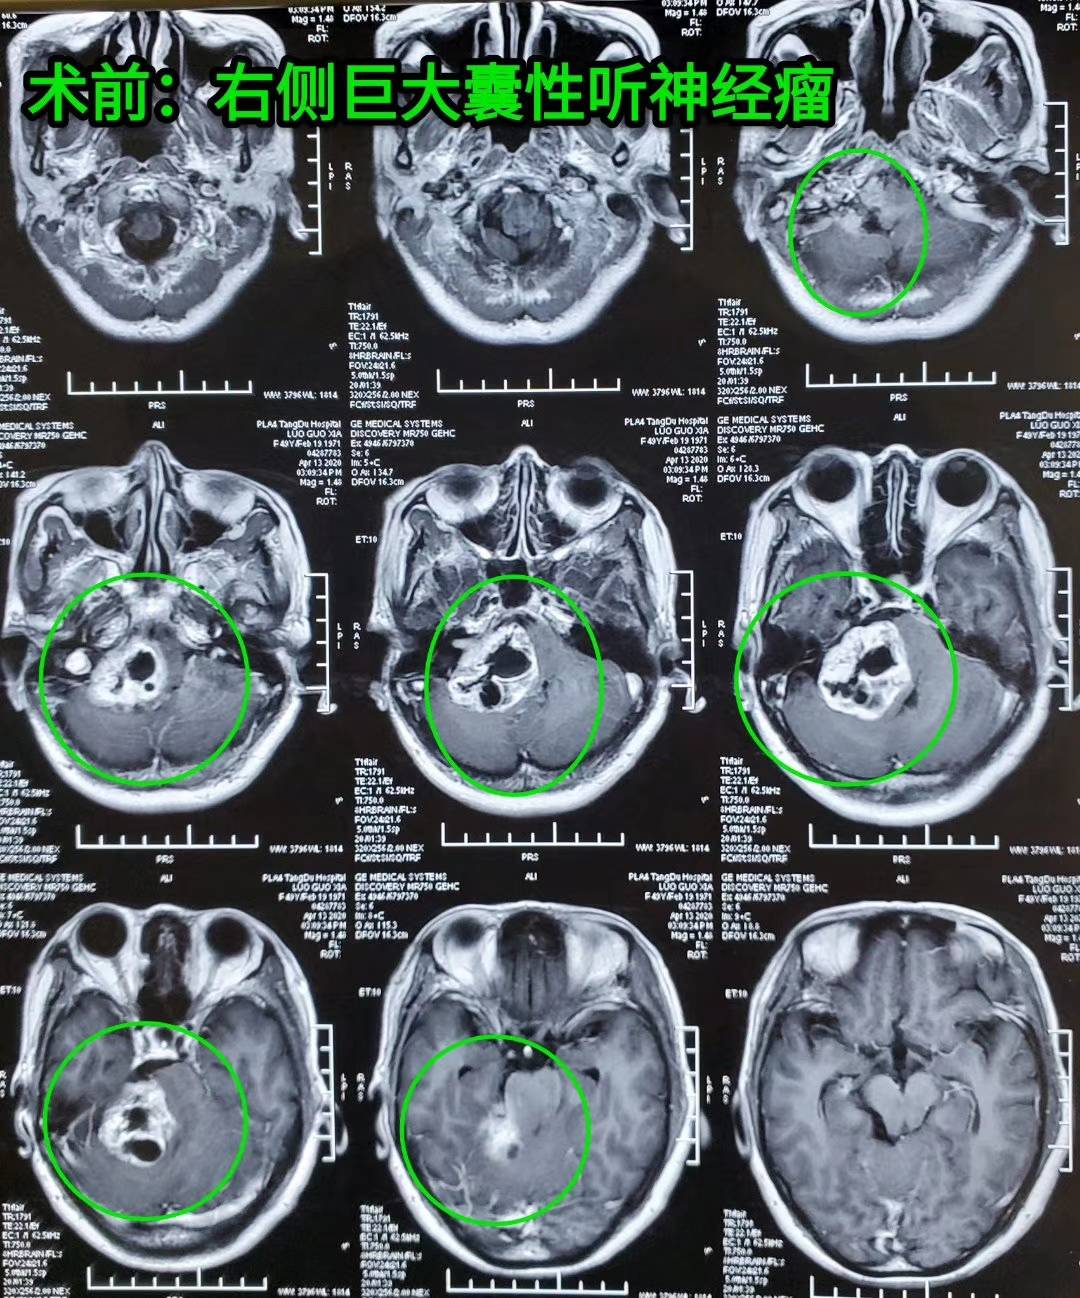

【病例分享】巨大囊性听神经瘤——唐都神经外科赵天智

图片尺寸1080x1298